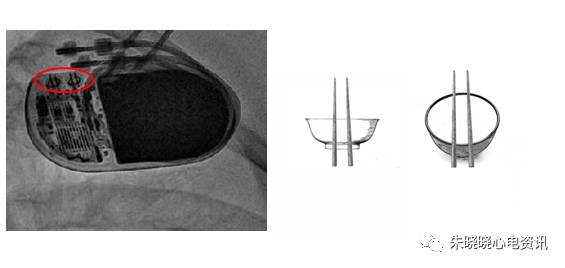

百多力起搏器接线部分和餐桌上的碗筷组合相似(图11)

图11 百多力起搏器